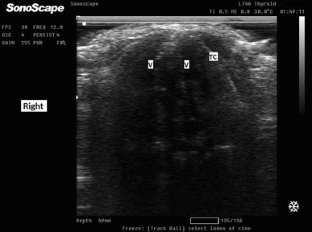

Fig. 1